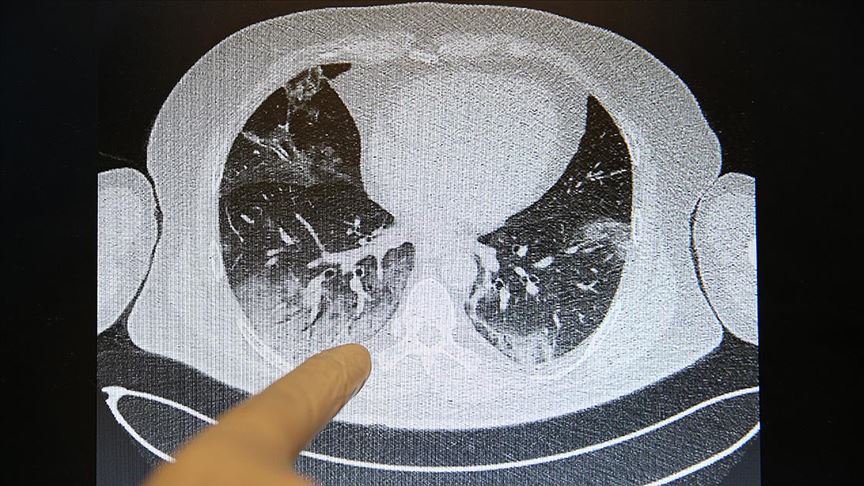

Akciğerlere verdiği tahribat nedeniyle solunum yetmezliği, nefes darlığı ve zatürreye neden olan yeni tip koronavirüsün (Kovid-19) vücuda verdiği zarar, tomografi görüntüleriyle de ortaya konuluyor.

Özellikle nefes darlığı şikayetiyle başvurduğu hastanede akciğer tutulumu olduğu tespit edilen hastaların, tomografi görüntülerinde Kovid-19'un verdiği tahribat ortaya çıkıyor.

Görüntülerdeki beyazlıklarla Kovid-19'lu bir hastanın akciğerindeki tutulumlar, iltihap birikmeleri ve organın yapısının bozukluğu ortaya konuluyor. Normal hastaların ise akciğerindeki elastik yapı dikkati çekiyor.

Elastik yapıya sahip akciğerlerde Kovid-19 nedeniyle oluşan tahribatlar sonucu zaman zaman organın kapasitesi küçüldüğü için hasta iyileştikten sonra da nefes almakta güçlük çekip, yürümekte zorlanabiliyor.